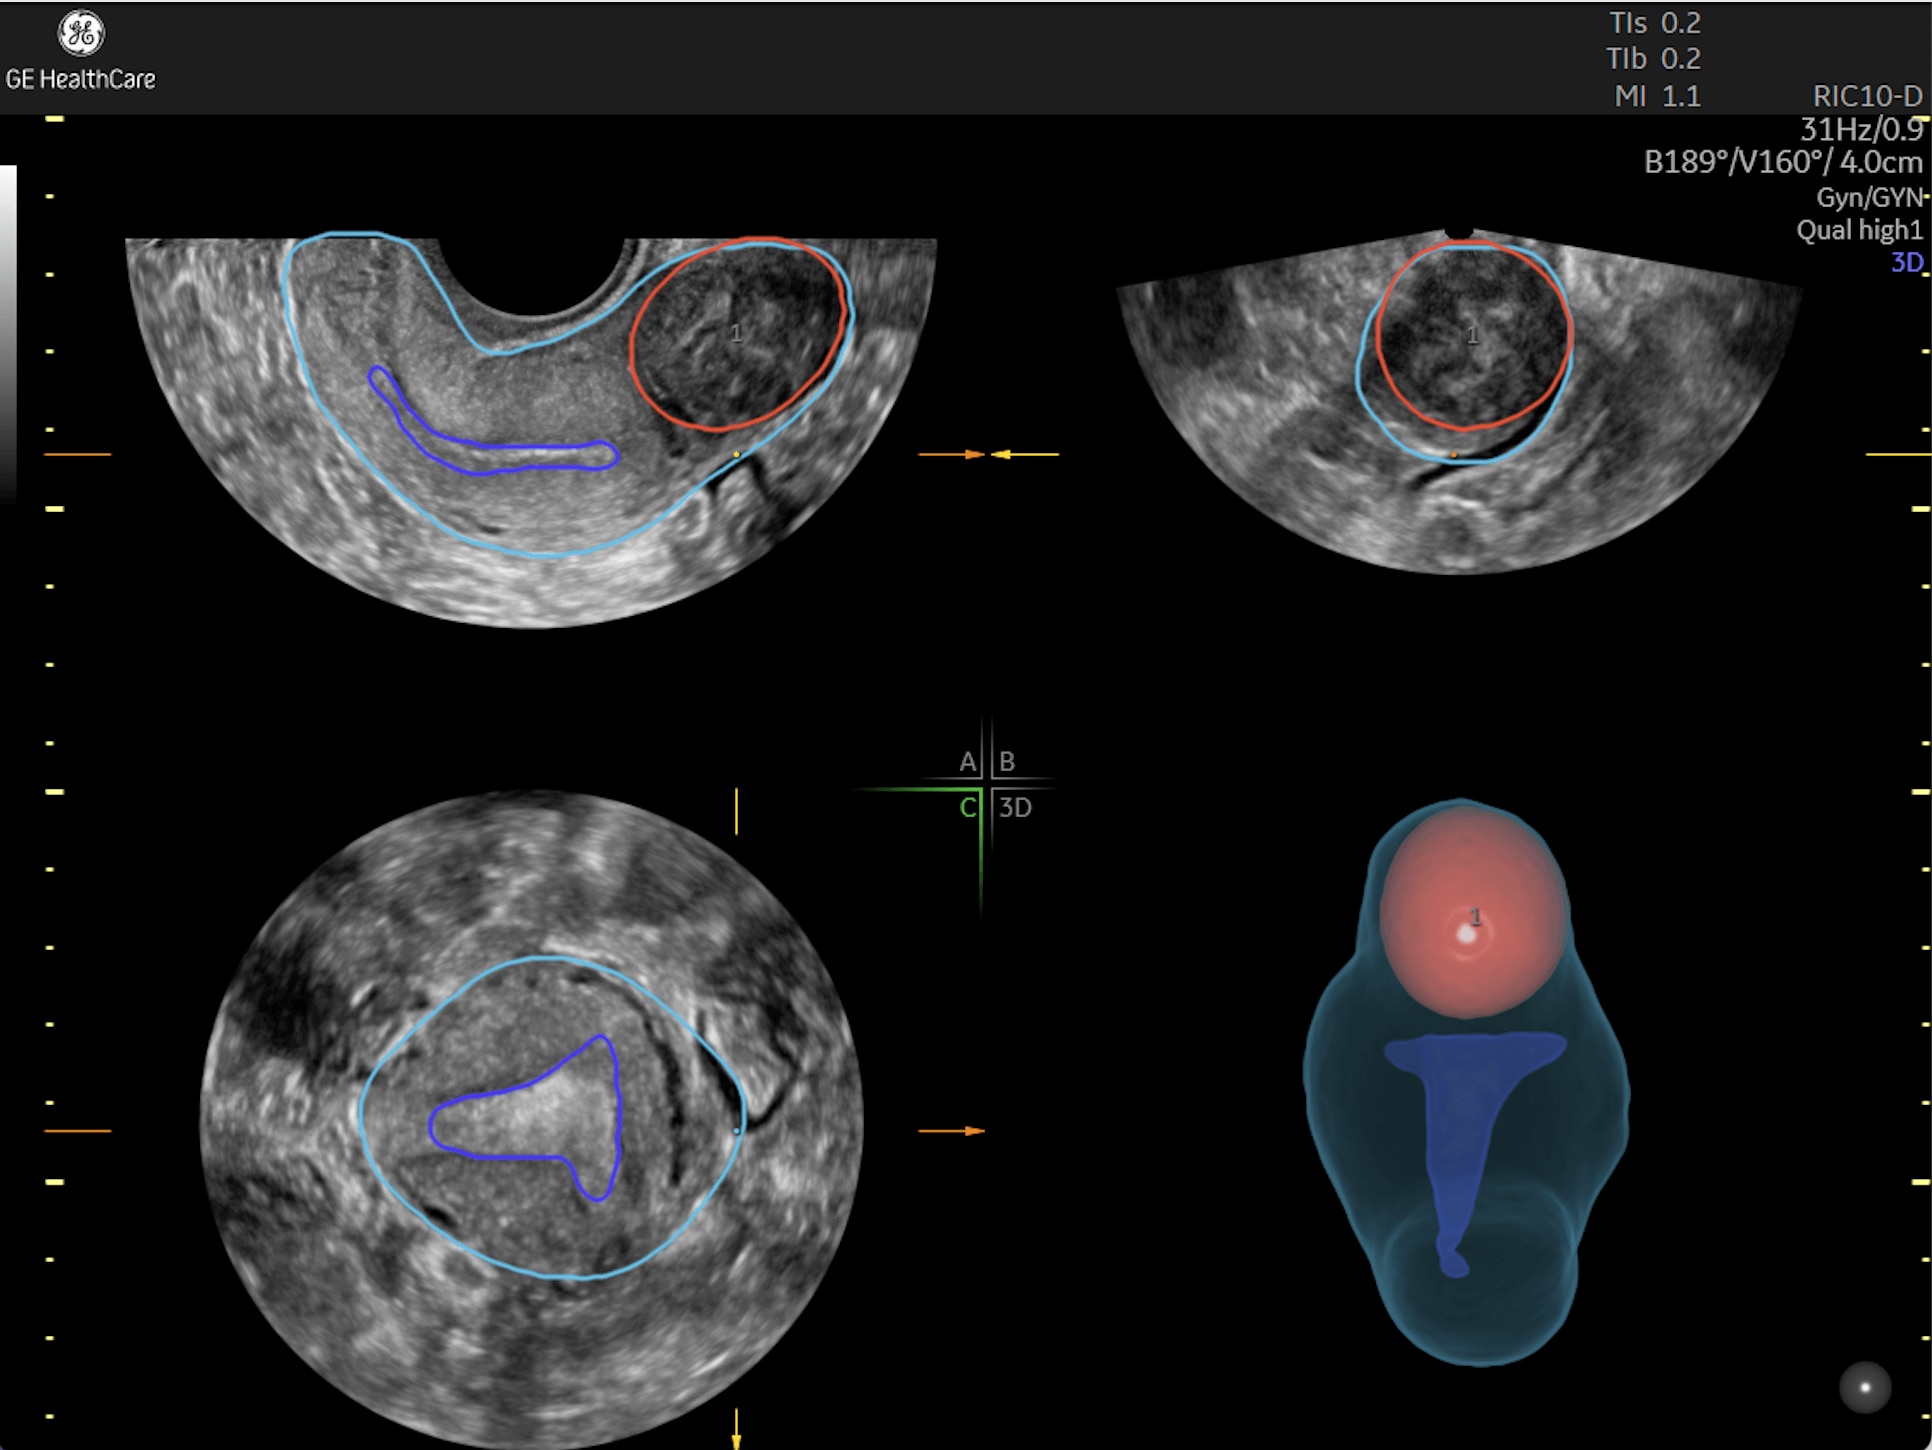

Amplify imaging performance and simplify scanning with our most advanced architecture

Refine Clinical Insights

Extraordinary clarity and definition so you can focus on early detection and intervention.

Faster.Sharper. Clearer.

Faster.Sharper. Clearer.